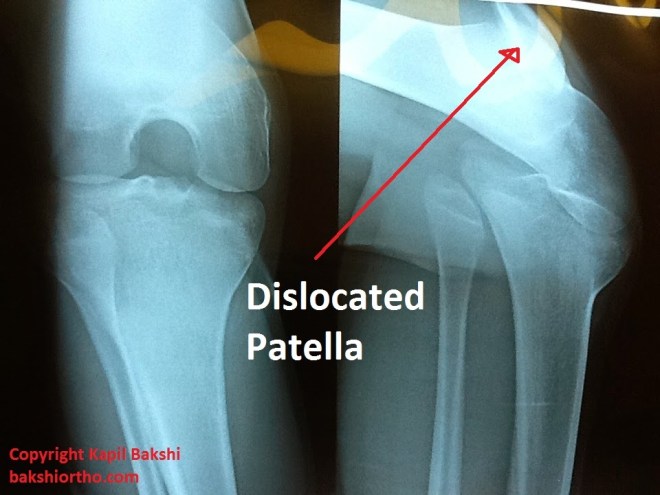

Dislocation of Patella with Subluxed Knee